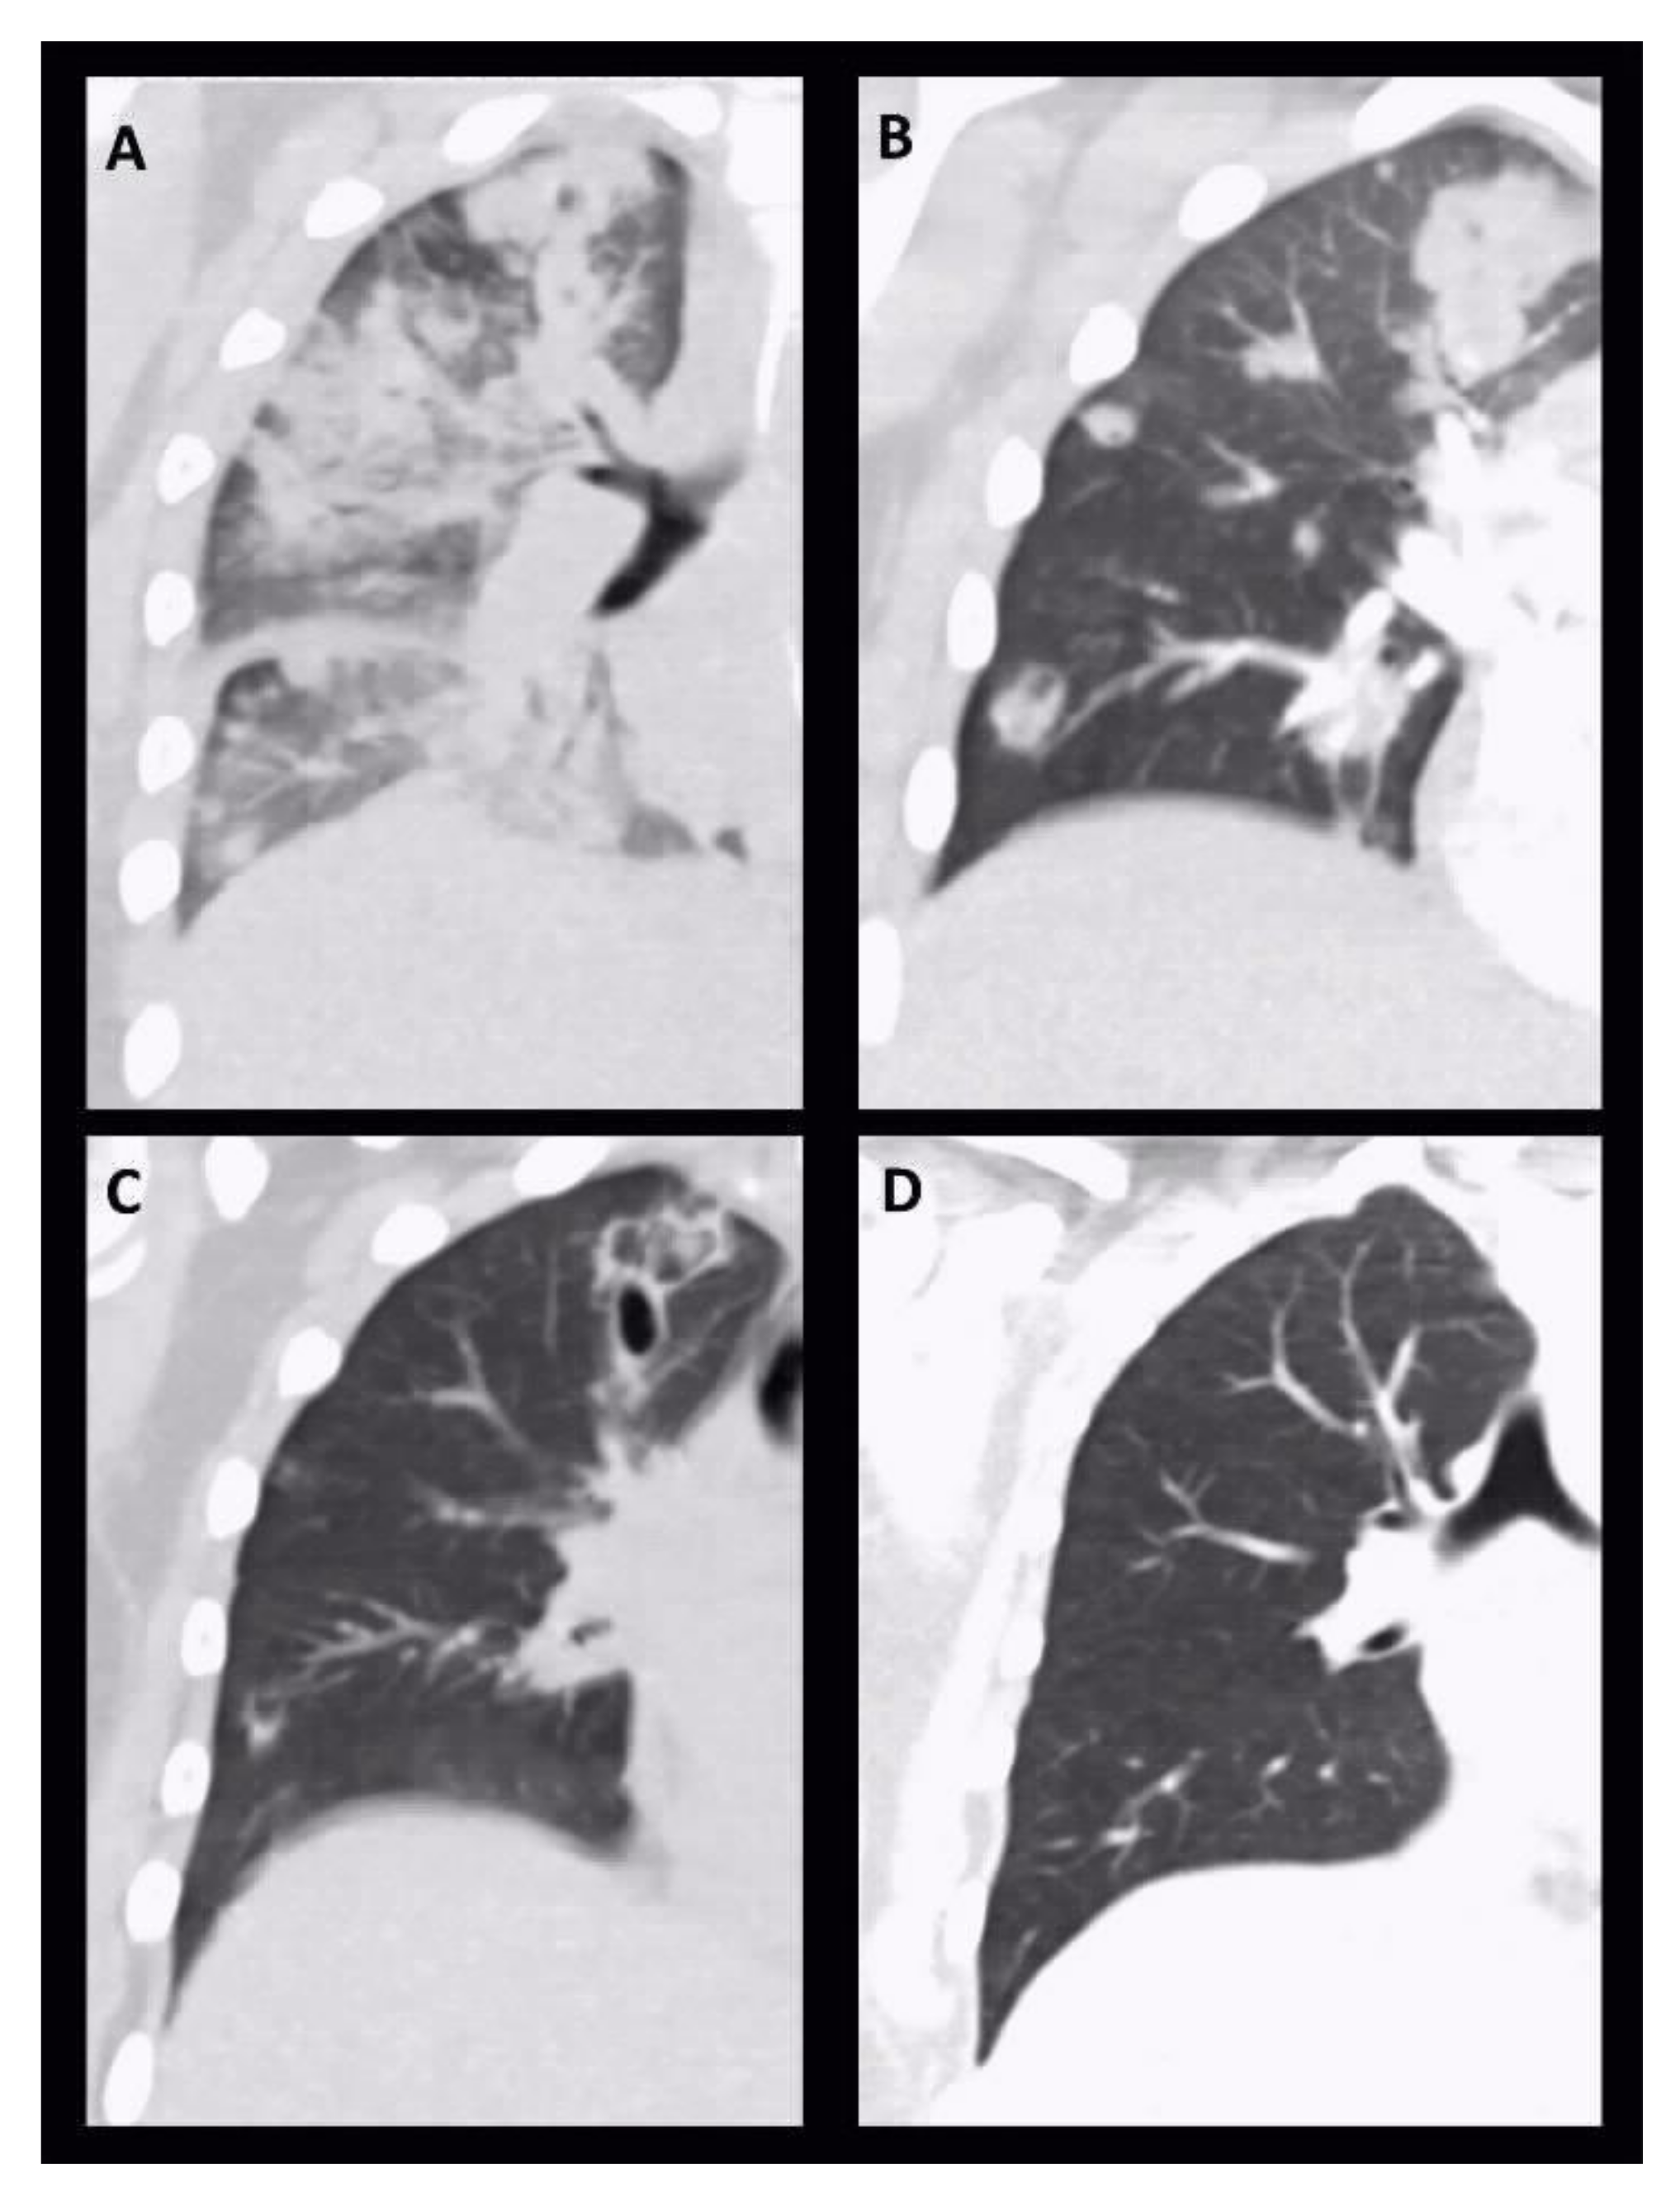

A CT scan showed extensive bilateral patchy areas, subpleural and peribronchovascular consolidations with surrounding ground-glass opacity, extensive consolidations in the lower lobes of both lungs matching to a severe pneumonia and clinically emerging ARDS. Moreover, it showed an extensive sinusitis of the right sinus frontalis, maxillaris and right cellulae ethmoidales. The images of Figure 1 show the radiological evidence in the performed chest X-rays, Figure 2 the sequential CT imaging.

Figure 2.

Serial chest CT images: Coronal reconstruction of serial chest CT images on day 1 (A), day 6 (B), day 17 (C) and day 39 (D). On initial CT scan periobronchovascular infiltrations with beginning consolidations were detectable. During follow up consolidations became more circumscribed with starting cavitation and abscessing, respectively. In the further course, pneumatoceles initially appeared (C), which completely resolved after treatment (D).

With persistent clinical critical condition and elevated levels of CRP (19.1 mg/dL), procalcitonin (7.35 μg/L) and leukocytes (22.4 Gpt/L) a whole-body CT scan was initiated for reevaluation 5 days after admission. It showed bipulmonary diffuse disseminated abscess-forming round foci with an increasing consolidation and abscess formation in comparison to the initial CT scan at admission (Figure 2).